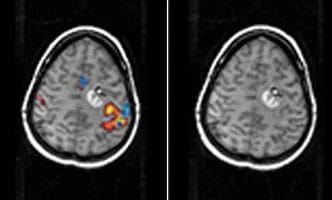

FMRI-cover

FMRI